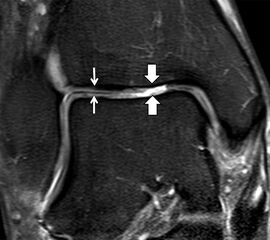

Jedoch findet man sich auch hier mit dem Problem der in den Standard-Projektionen schräg verlaufenden Syndesmose konfrontiert. Der oligofaszikuläre Aspekt der vorderen Syndesmose kann in der axialen Schnittebene eine zum Verwechseln ähnliche Morphologie wie eine Ruptur aufweisen (Abb. 15 b und c). Doppelangulierte Schnitte entlang der Achse (schräg koronar/schräg sagittal) lassen hingegen eine eindeutige Beurteilung der Bandstrukturen zu (Abb. 16) und verbessern die Syndesmosendiagnostik.

Bezogen auf die Transversalebene verläuft die Syndesmose ca. 30° schräg cranio-caudal anguliert (Abb. 15 a). Häufig lassen sich drei Hauptfaszikel differenzieren: das kürzeste superiore, das stärkste mittlere und das längste kaudale Faserbündel. Ein akzessorisches Bündel, das anteriore-inferiore, tibiofibulare Ligament (AITFL) oder auch Bassett-Ligament wird in 80-94% der Patienten nachgewiesen 8. Dies weist einen unmittelbaren Bezug zur anterolateralen Talusschulter auf (Abb. 17). In Kombination mit einer Außenbandinstabilität und konsekutivem, talarem Vorschub kann dieses zu einem Impingement an der anterolateralen Taluskante führen mit nachfolgender chondraler oder osteochondraler Läsion.